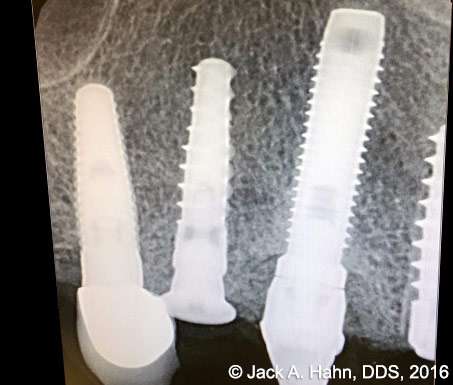

CASE #4 Trauma Case – Central Incisors Internal / External Resorption

Implants, that replace failed endo- or perio-compromised teeth, have a MUCH higher success rate with laser decontamination of the osteotomy site. LightScalpel laser surgical and perio laser tips ensure excellent access to extraction socket for the optimum removal of granulation tissue and socket decontamination (protocol involves manual curettage of the socket with alternating rinsing and lasing).

The patient, a 17-year-old female was involved in a water slide accident 3 years ago. As a result, both central incisors were avulsed and an endodontist replanted them. Both teeth exhibited internal and external resorption. Dr. Hahn extracted both central incisors, removed all the root fragments and sanitized the sites with the LightScalpel laser which also eliminated any granulation tissue. The #8 area was prepared to place a Hahn 4.3×13 Implant and #9 was prepared for a Hahn 3.5×13. 3mm tall Hahn healing abuts were placed slightly below the gingival-tissue level to help develop an emergence profile when at the restoration time in 4 months. Upon seeing the x-ray, Dr. Hahn tightened the healing abutment on #9 to be sure that it was completely seated on the implant. 45nucm. stability was achieved on both implants. He then placed some bone putty to seal any openings. To be on the safe side, he decided to place a temporary partial instead of immediate temporary prosthetics.